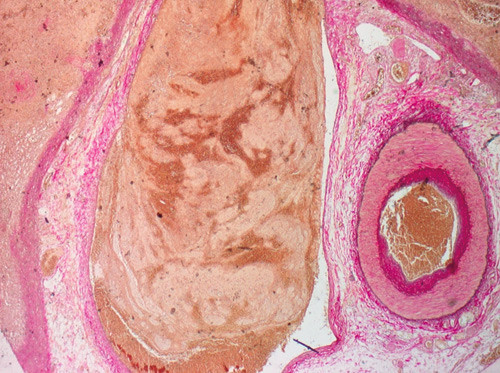

Histologisk undersøkelse av milten viste nekrose med partiell karnekrose (fig 2), histiocystiske granulomer og, sekundært til dette, trombotiske vener (fig 3). Resultatene ble tolket som mulig Wegeners granulomatose. En biopsi fra nesesvelget viste karulcerasjoner og blandet granulomatøs inflammasjon. I tillegg fant man en proteinuri (1,5 g/døgnurin) som gjenspeilte nyreaffeksjonen. Oftalmologisk og dermatologisk undersøkelse viste ellers normale funn. Vaskulittprøver i blod viste forhøyet C-ANCA (12U/ml, normalt < 6 U/ml). Kliniske, histologiske og biokjemiske funn førte til diagnosen Wegeners granulomatose.